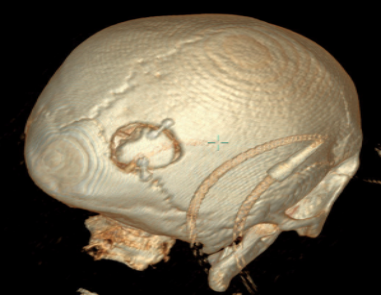

1.神经内镜手术创伤更小。以基底节区脑出血为例,传统的额颞部问号形切口,其长度至少要达到15cm 以上,切开颅骨大小约为8×10cm。而神经内镜手术切口长度仅需3 - 5cm,切开颅骨直径大小约 3cm,创伤明显更小。

在神经内镜治疗脑内血肿手术中,手术通道一般建立在额中回,而额中回前部为相对功能哑区,通道方向与纤维束方向平行。这种顺纤维束的手术操作,减少了手术带来的神经功能副损伤,术后患者的恢复情况相较于传统手术更好。对于大量出血患者,在传统手术过程中,为追求最大程度的颅内减压,往往会去除颅骨骨瓣,待患者术后恢复平稳后,还需要进行再次手术进行颅骨缺损的修补。而神经内镜手术不需要去除颅骨骨瓣,避免了术后二期颅骨修补手术,降低了患者的经济负担。